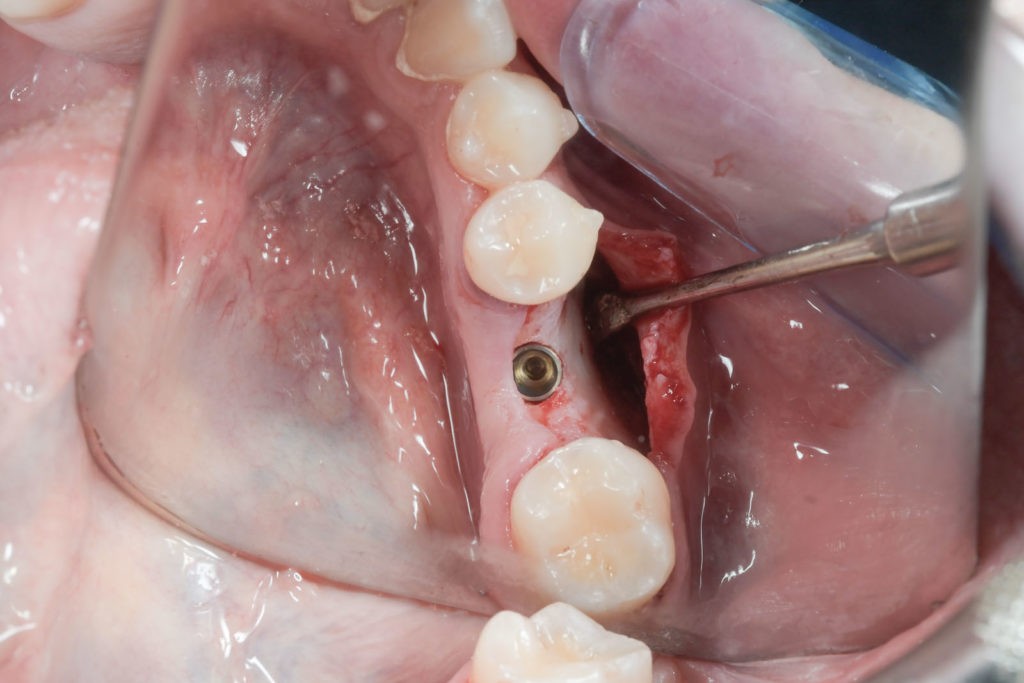

• Użycie drobin kości własnej do pokrycia ubytków na niewielkim obszarze, jak obnażenia gwintu implantu podczas implantacji, obnażenie korzeni zęba czy furkacji korzeniowych. Wiórki kostne pobierane są podczas zabiegu specjalnymi aplikatorami (skrobaczkami) z powierzchni kości szczęk i żuchwy.

Procedury te są stosowane w sytuacji niedostatecznej ilości kości, skutkującej odsłonięciem gwintu, podczas gdy wszczepiamy implanty stomatologiczne lub też jako zabiegi poprzedzające ich wprowadzenie.​